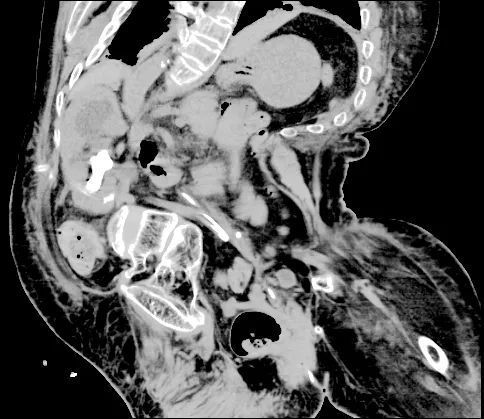

患者因“发现血肌酐升高1月余,发热1周”在我院肾内科住院治疗。住院期间行CT等检查明确肌酐升高、发热的原因是双侧输尿管存在结石梗阻。患者既往因小儿麻痹后遗症导致严重的脊柱侧弯畸形,直视下患者出现明显“驼背”,身体呈“折刀样”,X光平片下原本应该直立的脊柱呈“S”型改变,同时CT显示双肾明显异位、双侧输尿管明显扭曲,其中左肾甚至停留在脊柱偏右侧位置,与大血管十分贴近,给输尿管镜手术入镜及经皮肾手术穿刺带来极大困难和风险,稍有偏差就可能损伤到重要脏器及大血管。患者的脊柱侧弯畸形还合并有严重的胸廓畸形,畸形的胸廓导致肺和心脏的活动空间被大幅压缩,直接会引起心脏和肺的功能减退,麻醉过程中一旦出现意外,患者的心功能和肺功能衰竭会危及生命。不仅如此,患者还合并有重度贫血、高血压、脑萎缩、膀胱多发憩室等多种严重影响手术安全或操作的基础病。

▲患者的脊柱、胸廓明显畸形